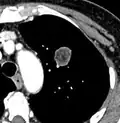

-

Low attenuating nodule (in this case a fat containing hamartoma).[9] -

Cavitation with relatively thick wall, in this case aspergilloma).[9]